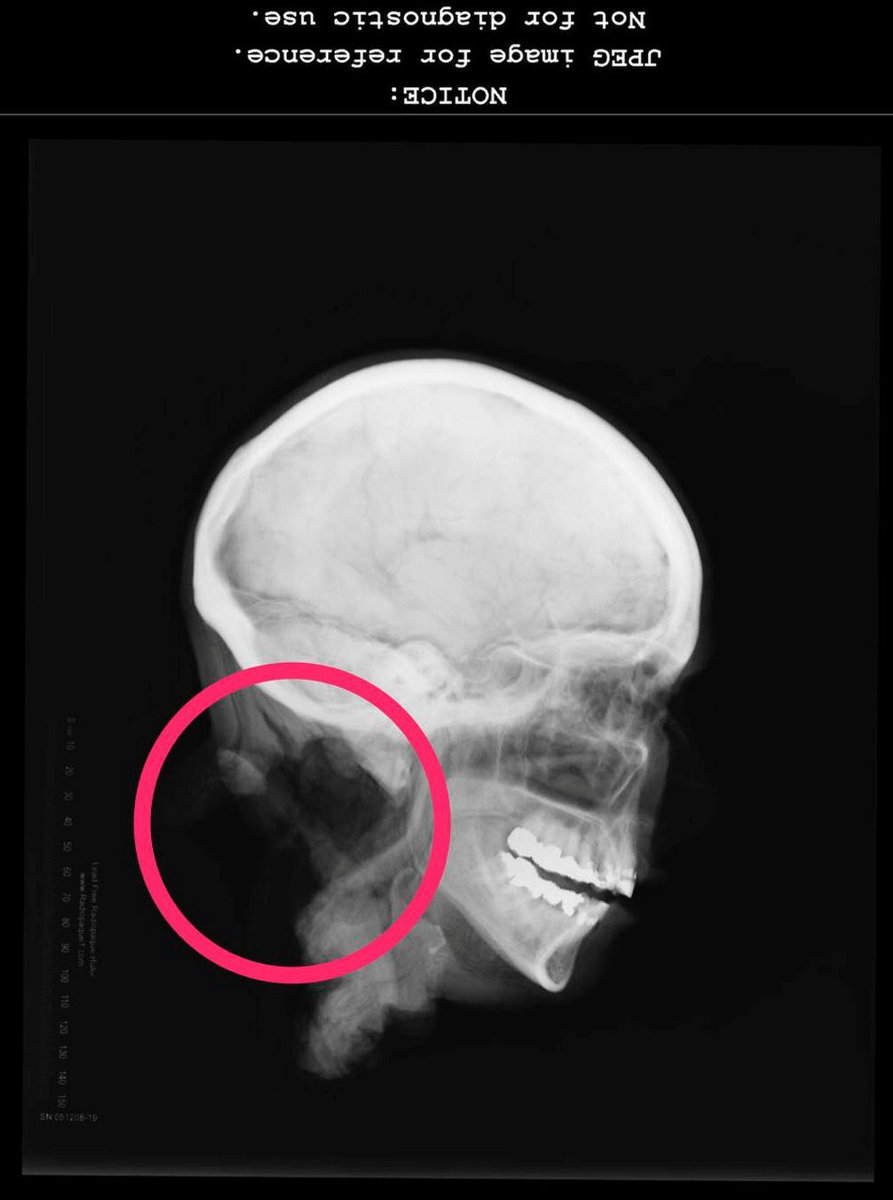

Authorities found a full set of teeth inside the woman’s mouth and took X-rays. Dentists at the University at Buffalo School of Dental Medicine examined the head and determined that work had been done on every single tooth – one of them as many as seven times.

Using one of three teeth they pulled, the dentists also found what they believe to be a filling compound that wasn’t available to dentists before 2004, meaning the woman likely died sometime thereafter. Based on their examination, dentists Raymond Miller and Peter Bush were able to posit a possible profile of Jane Doe: a lower-income woman who had many cavities and may have grown up where the water wasn’t fluoridated.

She probably lacked top-notch dental insurance that would have covered crowns, but may have had a cheaper plan that paid for fillings, Miller said. The work on her mouth was what Miller called “patchwork dentistry,” in which problems are addressed only when necessary. Still, the work was well done, both dentists agreed.

“Somebody took good care of her,” Miller said. “Every tooth is filled or fixed in her mouth.” The extent of that work would make her “an easy ID if we had any kind of information about her.”

X-rays of the head clearly show the vertebrae are missing.